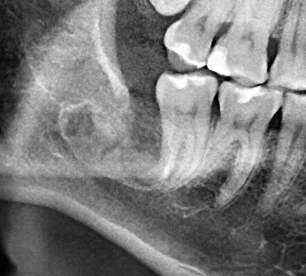

☆本院特別巨資增設 ”千萬級3D AI透視電腦斷層”,並配合“成骨膠原蛋白”施作 (上述兩項目前健保無給付),讓您遠離神經傷害、口鼻竇(炎)相通...等併發症,除健保之外,難免會有避免併發症風險的自費項目,網路上經常會有看到智齒拔完後唇麻、舌麻、口鼻竇相通等併發症,在本院嚴格自我要求下,此類併發症在本院幾乎趨近於零。

(兩條紅線中間黑色區域即為神經管)

外面拔完時常術後唇麻舌麻,本院發生趨近於零